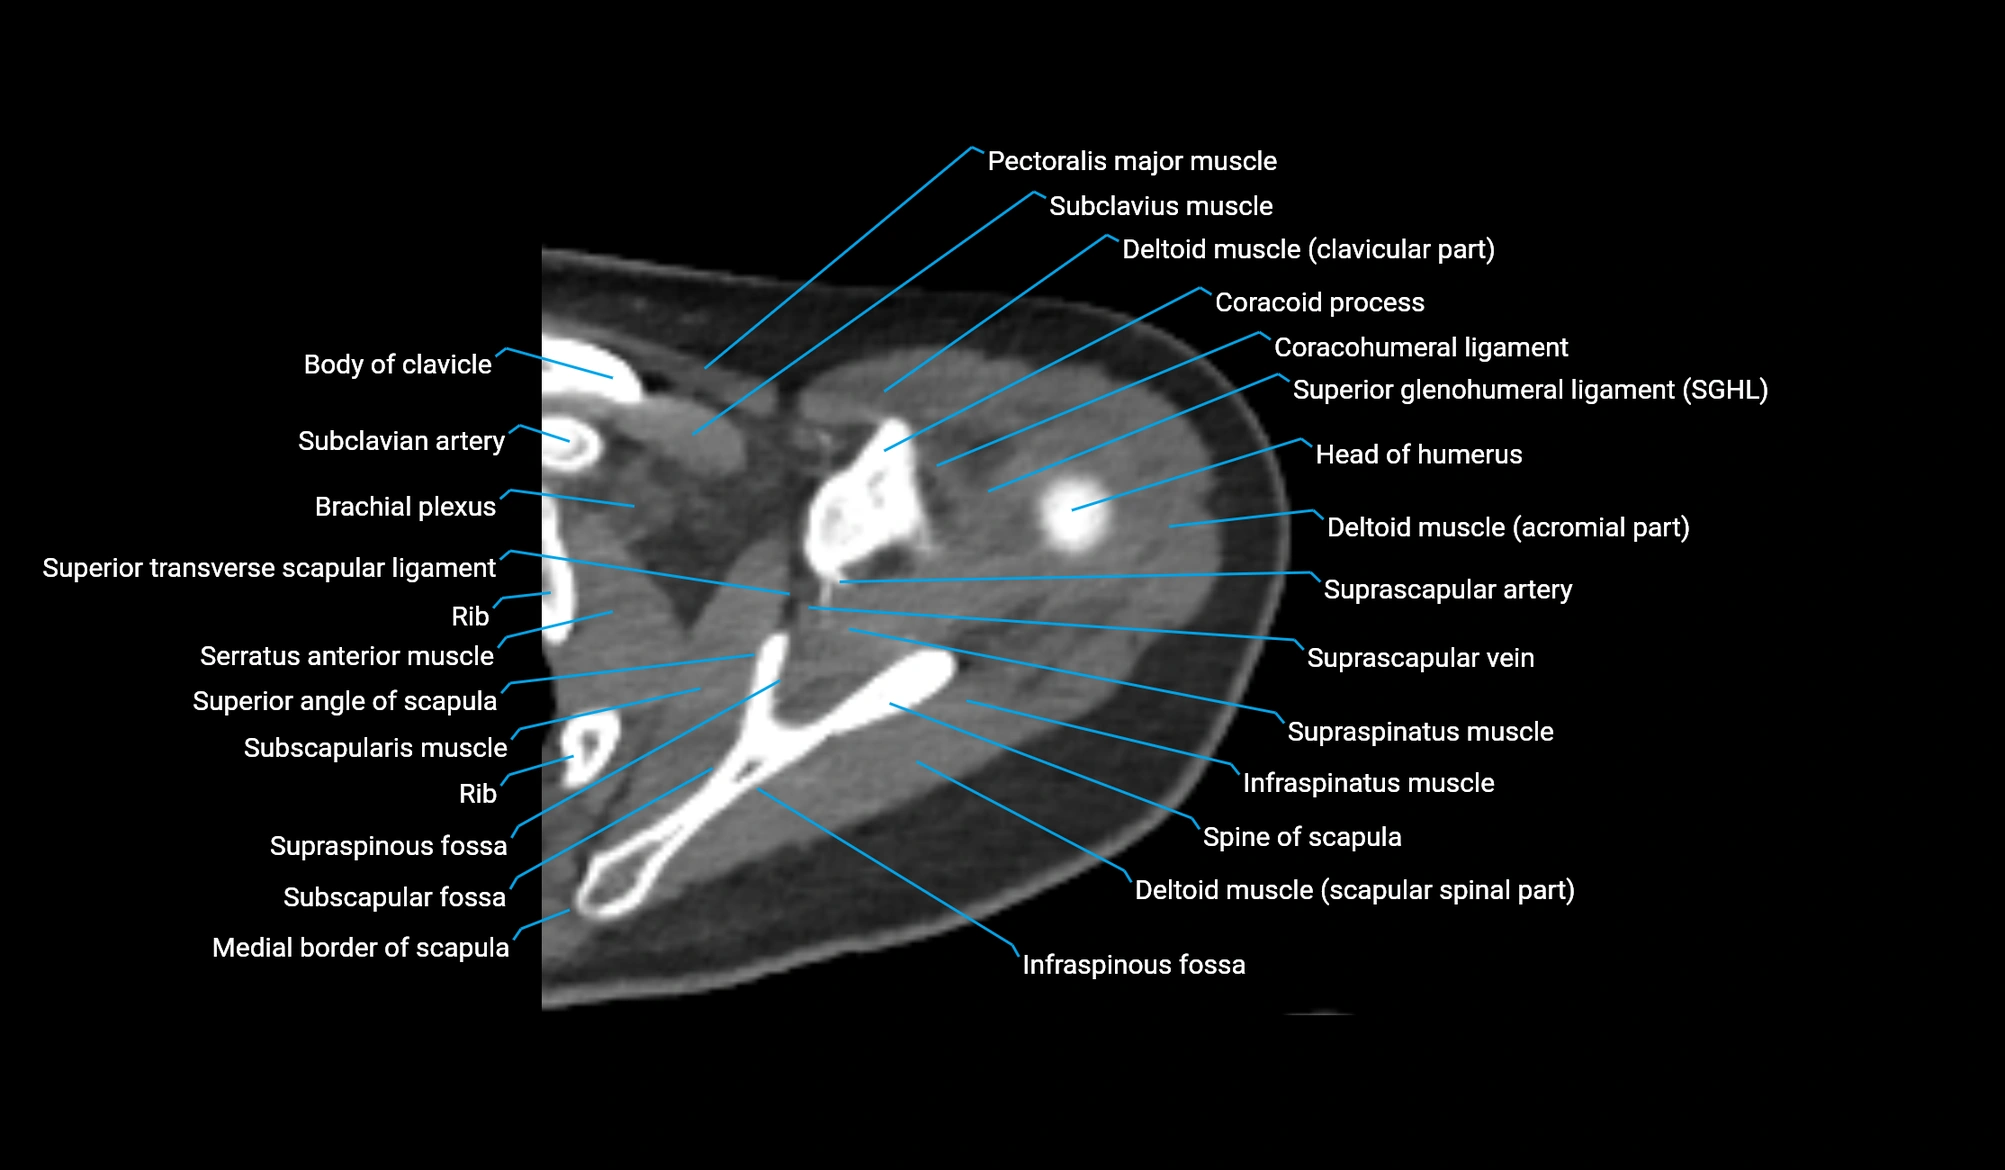

- Brachial plexus

- Clavicular part of deltoid muscle

- Coracohumeral ligament

- Coracoid process of scapula

- Head of humerus

- Infraspinatus muscle

- Infraspinous fossa

- Lateral border of scapula

- Medial border of scapula

- Pectoralis major muscle

- Spine of scapula

- Subclavius muscle

- Subscapular fossa

- Subscapularis muscle

- Superior angle of scapula

- Superior glenohumeral ligament

- Superior transverse scapular ligament

- Supraspinatus muscle

- supraspinous fossa of scapula